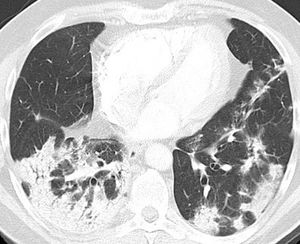

Patient 363-year-old white female with an unremarkable prior medical history. She presented on day 14 of her illness with shortness of breath. Her P/F ratio was 150 on arterial blood gas, and high-flow oxygen support was started through a reservoir mask. A CPAP was installed on the following day, and dexamethasone was prescribed. She completed a course of both azithromycin and amoxicillin-clavulanate. No clinical improvement was noted, and the patient received a CT scan. The CT scan revealed a pattern of OP (Fig. 3), and corticosteroids were started at 1 mg/kg PO daily. After three doses, the patient was ventilating on low-flow nasal cannula. She improved considerably and had no dyspnea on exertion (Table 1).